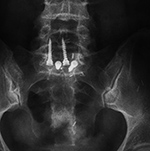

| Interspinous clamps (ILIF) at L4-5 |

Interspinous clamps (ILIF) at L4-5 |

| 67 year-old woman with lower lumbar spinal stenosis. The patient is wearing a TLSO brace. |

76 year-old woman treated for degenerative spondylolysthesis at L4-5. The patient is wearing a TLSO brace. |